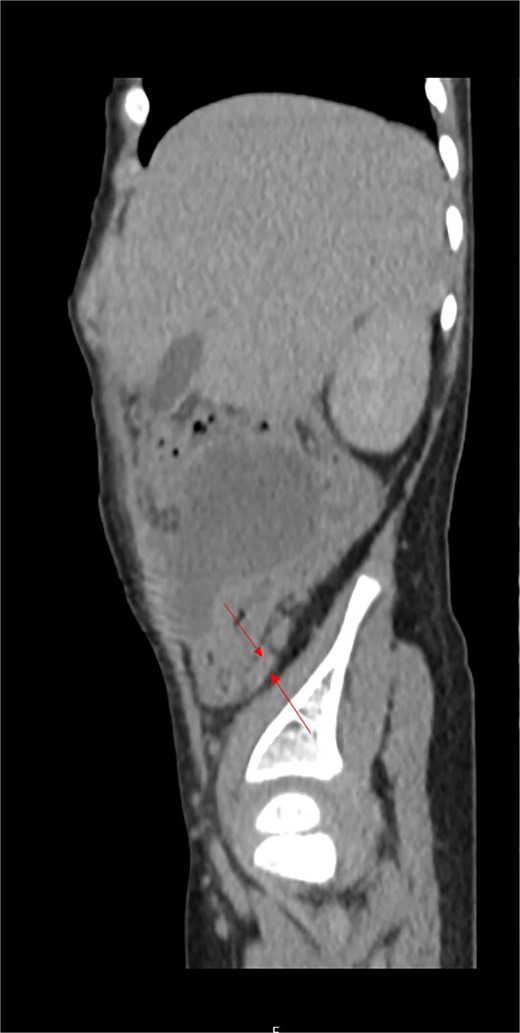

Histopathologic examination confirmed severe acute transmural appendicitis with thick fibrinopurulent deposits in one specimen (Fig. 2A and B) and secondary appendicitis with fibrinopurulent deposits on the serosa in the other (Fig. 2C and D). The patient had an uneventful postoperative recovery and was discharged in stable condition after 8 days. Intraoperative discovery of a duplicated vermiform appendix prompted a reevaluation of the preoperative CT scan, which revealed an additional appendix in a typical retrocecal position, measuring 24.1 mm in length, that was not initially detected (Fig. 3).

Postoperatively analyzed preoperative contrast-enhanced sagittal abdominal CT scan detected a retrocecal 24.1 mm long tubular structure (a smaller second secondary inflamed appendix) with a transverse diameter of 5.6 mm and a wall thickness of 1.8 mm adherent to/inseparable from the dorsal wall of the cecum (labeled).